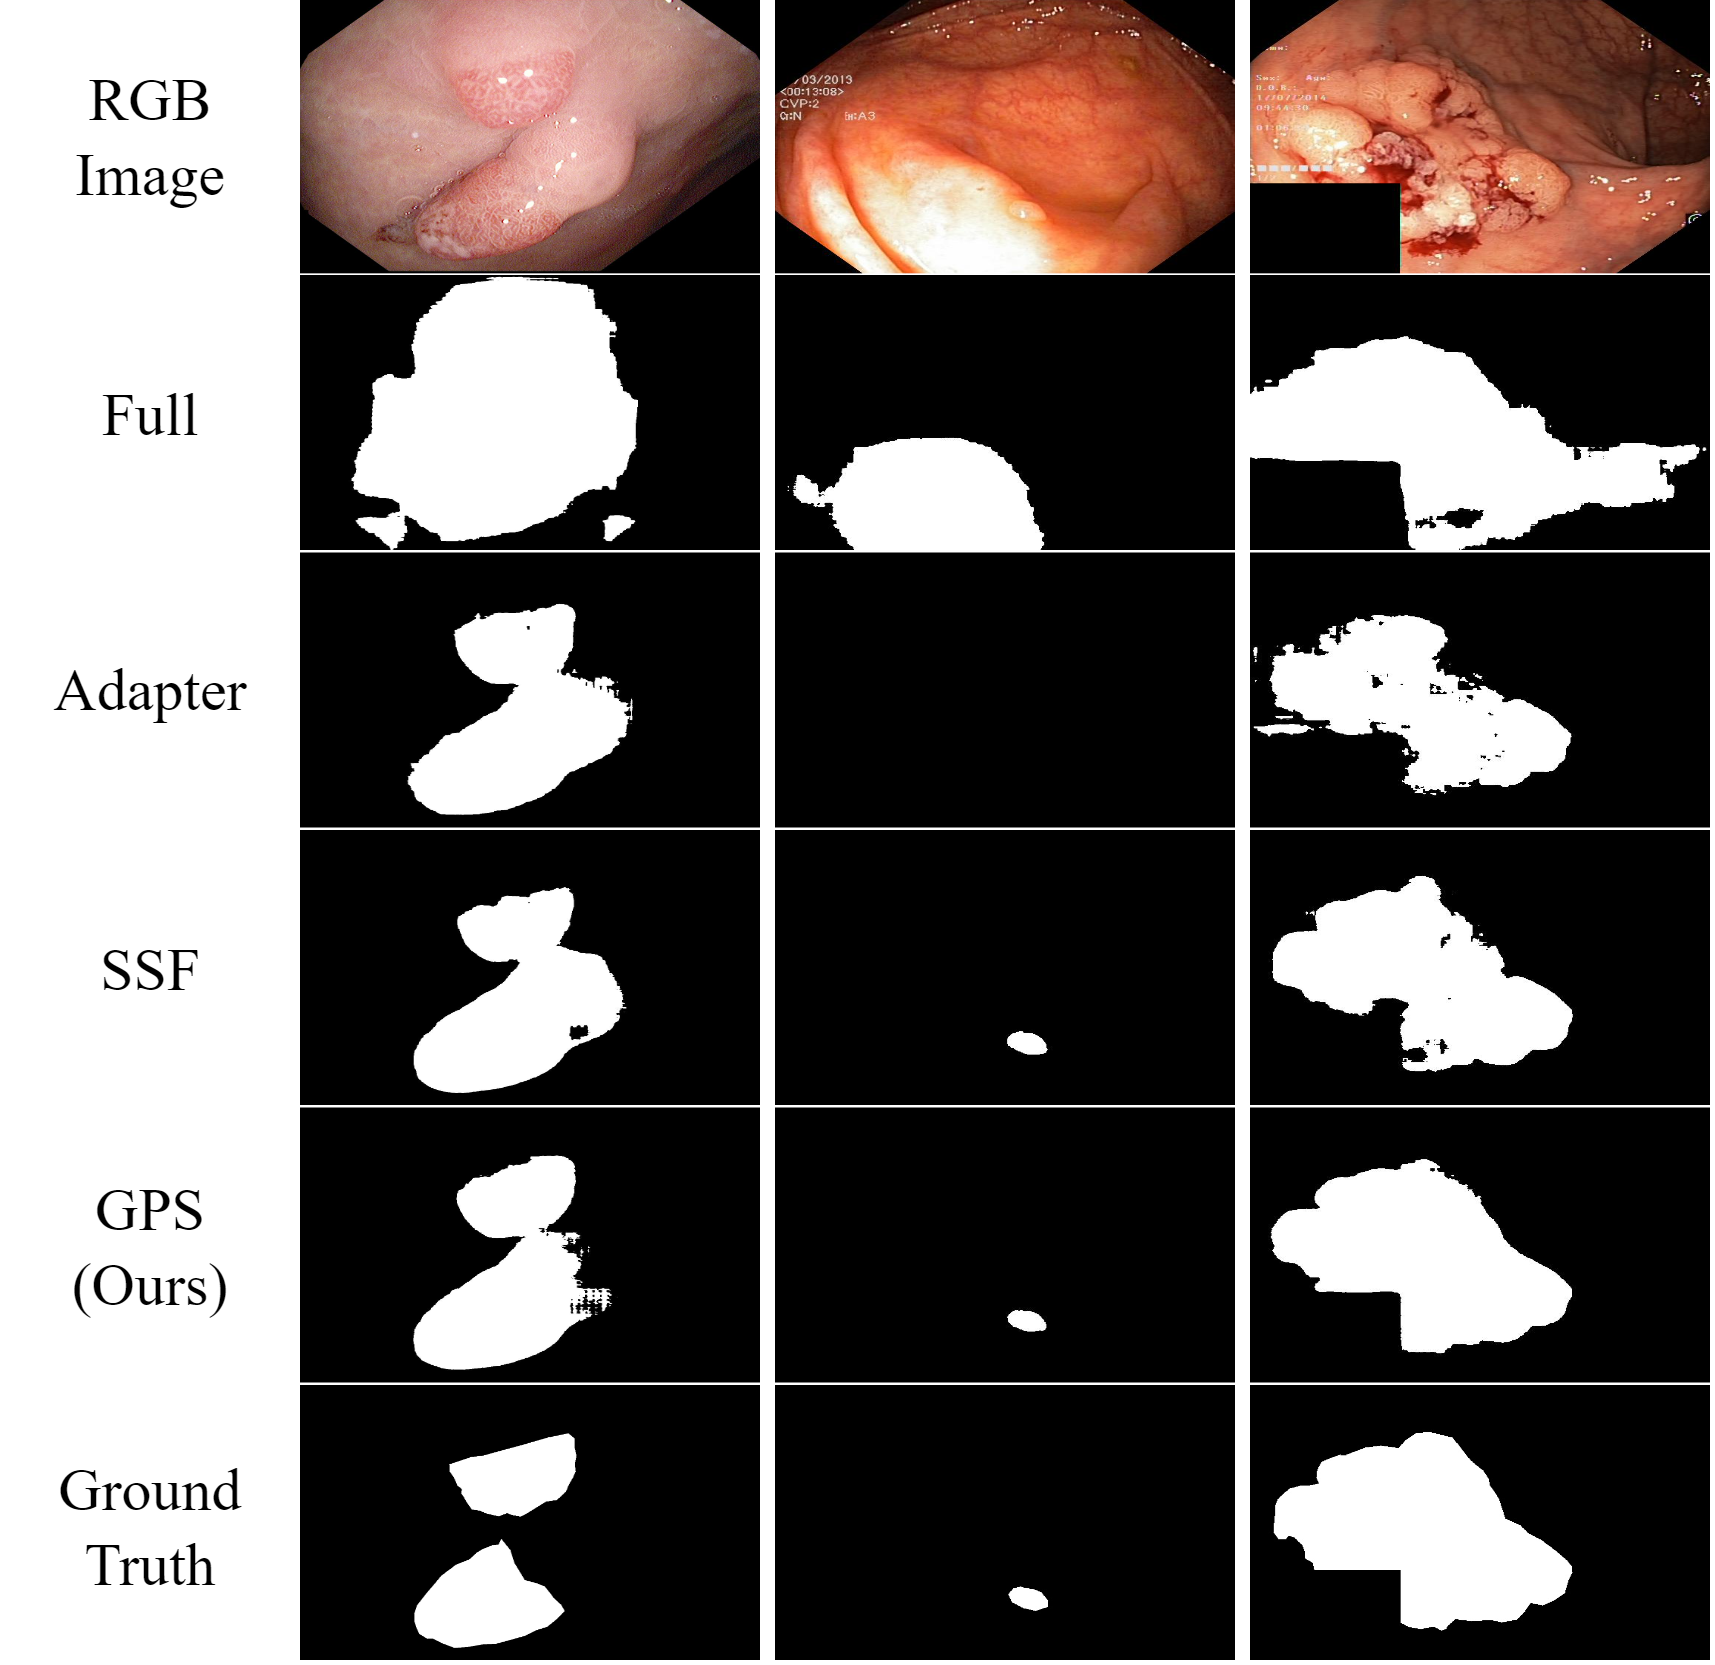

In addition to visual classification tasks, we also explore our method for the task of semantic segmentation. Segment Anything Model (SAM) [50] is a strong foundation model for segmentation. It is pre-trained on a large-scale dataset enabling powerful generalization. However, several studies, e.g. [6], have reported poor performance of SAM on medical segmentation tasks such as polyp segmentation [41]. To address this limitation, they proposed employing Adapter to effectively fine-tune SAM for downstream medical segmentation tasks. Following their experimental setup, we applied our method to SAM and conducted a comparative analysis with other PEFT approaches. Our GPS yielded exceptional results, as shown in Tab. 5 and visually depicted in  Fig. 7 (See Supplementary for more case visualization).

Refer to caption

Figure 7: The Visualization of Polyp segmentation task. Our GPS can still handle difficult segmentation cases compared with others.